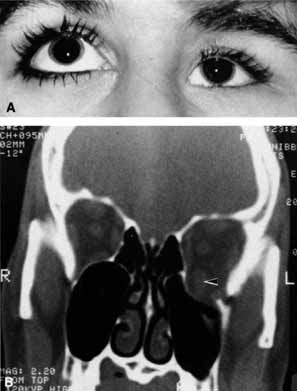

Anosmia caused by damage of cranial nerve I may be a helpful symptom of ethmoid or sphenoid sinus tumors invading the orbit (Fig. 20).44 Olfactory groove meningiomas and esthesioneuroblastomas may also present with anosmia prior to developing vision loss.45 Trauma that involves the orbit and is associated with anosmia should be considered a basilar skull fracture with potential for cerebrospinal fluid leak until proven otherwise (Fig. 21).

Fig. 21 A 21-year-old man sustained a skull fracture from a motor vehicle accident 2 months prior to this examination. The patient describes anosmia since the accident. Computed tomography discloses a large medial wall orbital fracture extending through the cribriform plate (arrow). Orbital reconstruction was performed through a frontal craniotomy where dura was found incarcerated within the fracture. The orbital fracture was repaired by cranial bone grafting.